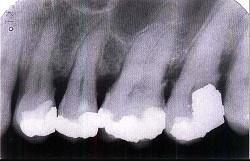

问题 牙槽骨水平型吸收的特点是 ( )

选项 A.常形成骨上袋 B.是最常见的吸收方式 C.牙槽间隔、唇颊侧或舌侧的嵴顶边缘呈水平吸收 D.牙槽嵴高度有明显降低 E.以上均是

答案 E